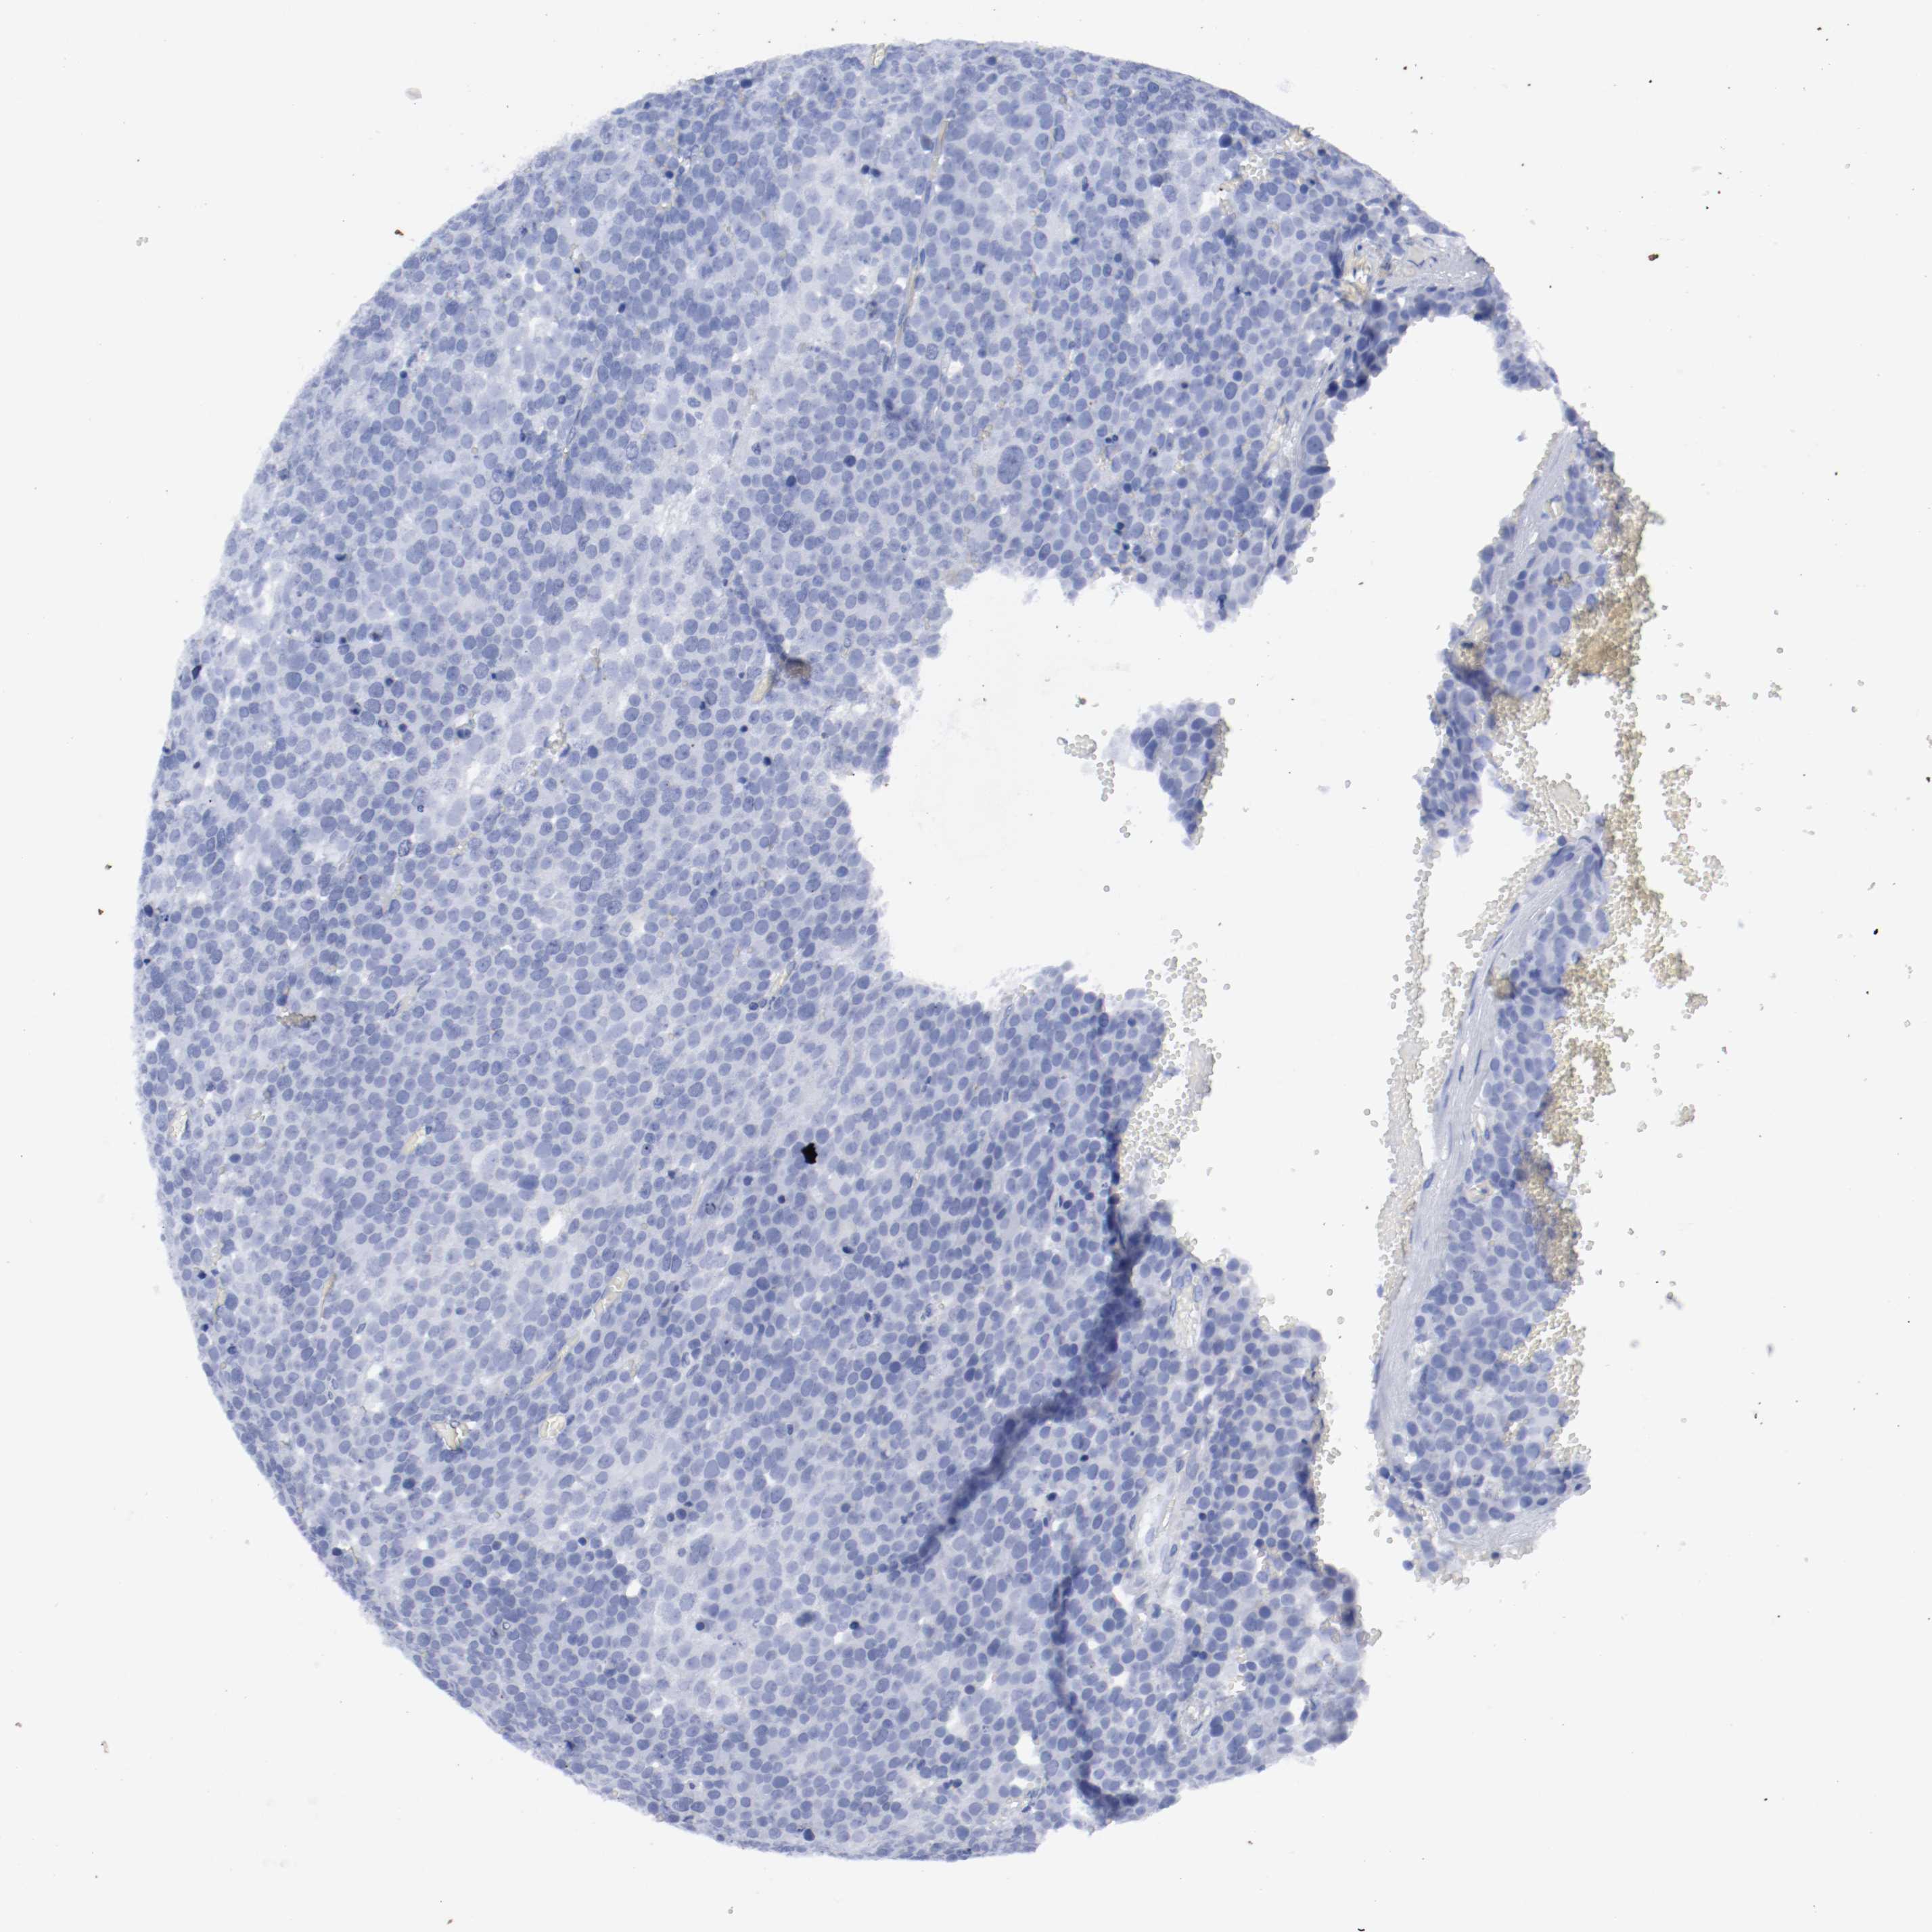

TESTIS CANCER - Protein expressioni

A mouse-over function shows sample information and annotation data. Click on an image to view it in a full screen mode. Samples can be filtered based on level of antibody staining by selecting one or several of the following categories: high, medium, low and not detected. The assay and annotation is described here.

Note that samples used for immunohistochemistry by the Human Protein Atlas do not correspond to samples in the TCGA dataset.

Antibody stainingi

Antibody staining in the annotated cell types in the current human tissue is reported as not detected, low, medium, or high, based on conventional immunohistochemistry profiling in selected tissues. This score is based on the combination of the staining intensity and fraction of stained cells.

Each image is clickable and will lead to virtual microscopy that enables deeper exploration of all samples and also displays staining intensity scores, fraction scores and subcellular localization as well as patient and tissue information for each sample.

Antibody HPA004109

Staining

High

Medium

Low

Not detected

Intensity

Strong

Moderate

Weak

Negative

Quantity

>75%

75%-25%

<25%

None

Location

Nuclear

Cytoplasmic/membranous

Cytoplasmic/membranous,nuclear

Carcinoma, Embryonal, NOS

Seminoma, NOS